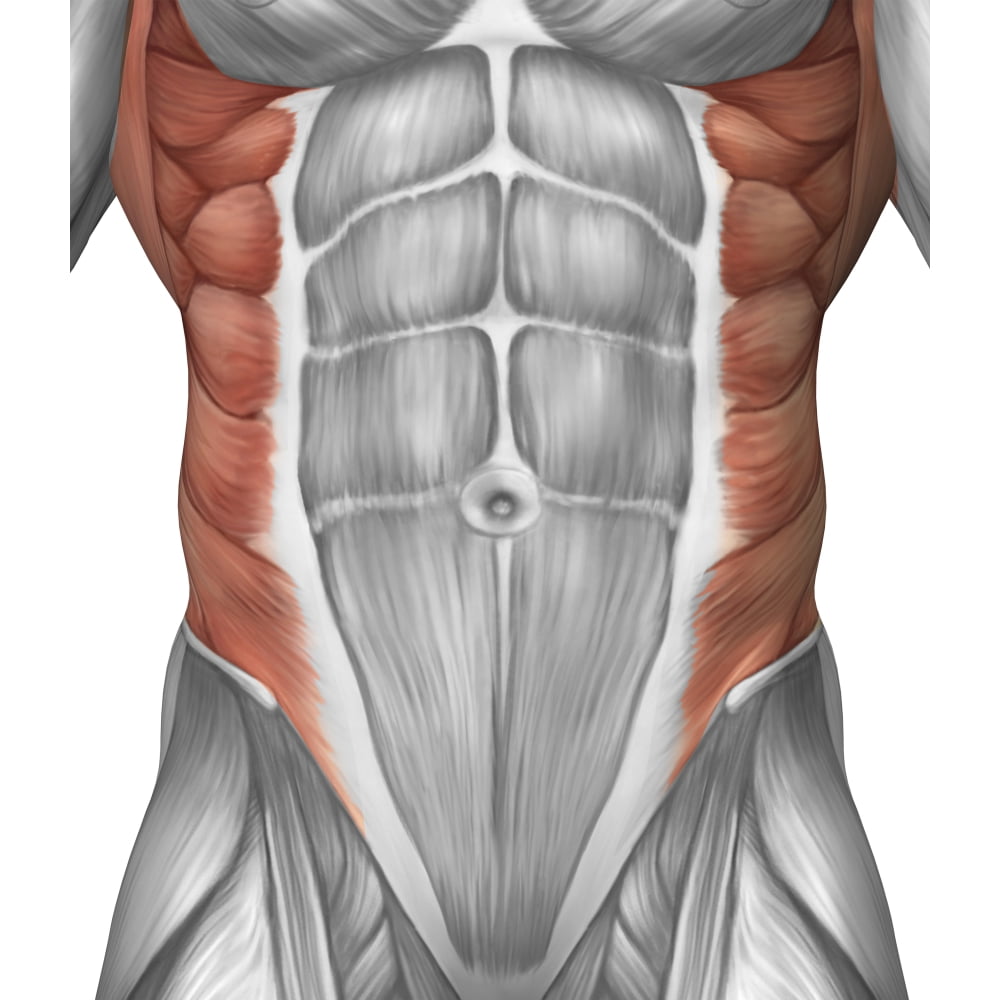

Abdominal Muscle Layers, Artwork - Stock Image - C010/7080 - Science

www.sciencephoto.comabdominal muscle layers

www.sciencephoto.comabdominal muscle layers

Map Of The Abdominals | FusionPilatesEDU.com

fusionpilatesedu.comabdominals map anatomy area layer

fusionpilatesedu.comabdominals map anatomy area layer